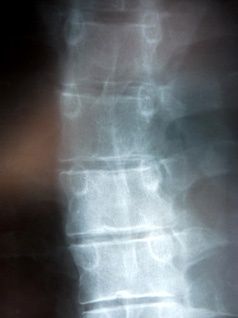

Alleine in Deutschland werden über 30.000 Operationen an der Bandscheibe vorgenommen und weltweit ist die Bandscheibenoperation der häufigste neurochirurgische Eingriff. Falls keine Lähmungen vorliegen, gibt es unter dem Strich jedoch keinen signifikanten Unterschied zwischen den Behandlungsresultaten dieses Eingriffs und dem konservativen (nicht-operativen) Vorgehen, wie etwa Akupunktur oder Medikamente oder Physiotherapie. Dies ist das Ergebnis der weltweit größten klinischen Studie mit 1244 Bandscheibenpatienten (Spine Patient Outcome Research (SPORT), 2006). Dass Wirbelsäulen-Operationen auch bei Fachleuten umstritten sind, weiß auch Professor Dr. Wehling [habilitiert in Orthopädie-Molekulare Medizin] nach Auswertung von circa 1.200 internationalen Publikationen (inklusive SPORT). „Kurzfristig können Operationen bei Bandscheibenvorfällen an der Lendenwirbelsäule helfen, mittel- und langfristig sind die Ergebnisse von operierten und nicht operierten Patienten jedoch gleich.“

Die Befunderhebung und die Ursachenbehandlung sind hierbei sehr wichtig. Meistens stellt sich eine totale Blockade des Lenden- und Brustwirbel-Bereiches heraus, was bei den meisten Menschen wegen einer Schwäche der Grundmuskulatur im Rückenbereich der Fall ist.

Während der Behandlung mit der muskulären Tiefenmassage - MTM nach Bergmüller und anschließendem Fango beginnen sich die ersten tief liegenden Muskelverhärtungen nach und nach zu lösen. Dadurch und mit Hilfe sanfter Chiropraktik sowie Bewegungstherapie kommt es zu einer Korrektur der fehl gestellten Wirbel. Zusätzlich wird nach Eintritt der Beschwerdefreiheit die Muskulatur über gymnastische Übungen (maximal fünf Minuten täglich) langfristig stabilisiert.